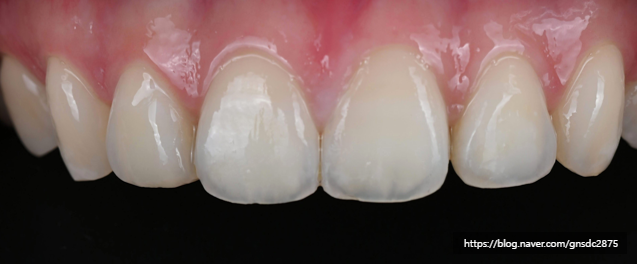

#CASE 02

백색반점이 있는 길이가 다른 앞니

다음 환자분도 양앞니의 백색반점과

미세하게 다른 치아 길이를

앞니통합치료 뉴티스로 개선하였습니다.